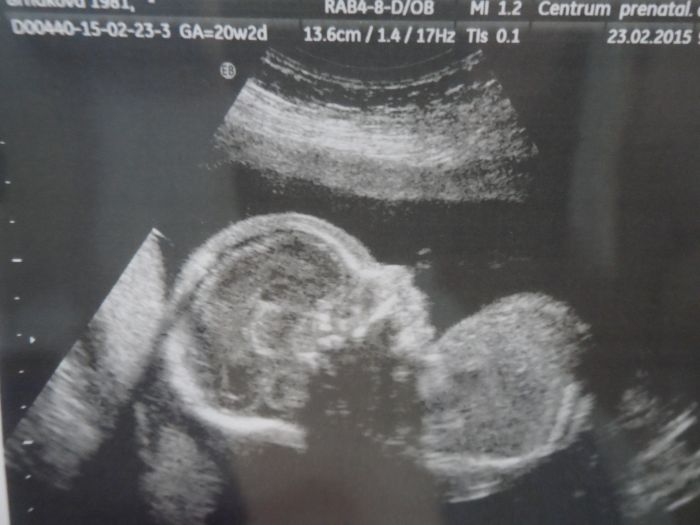

Honzíček-21tt(vúnoru),jedna a tatáž fotka ,ale papír je lesklý,špatně se přefocuje